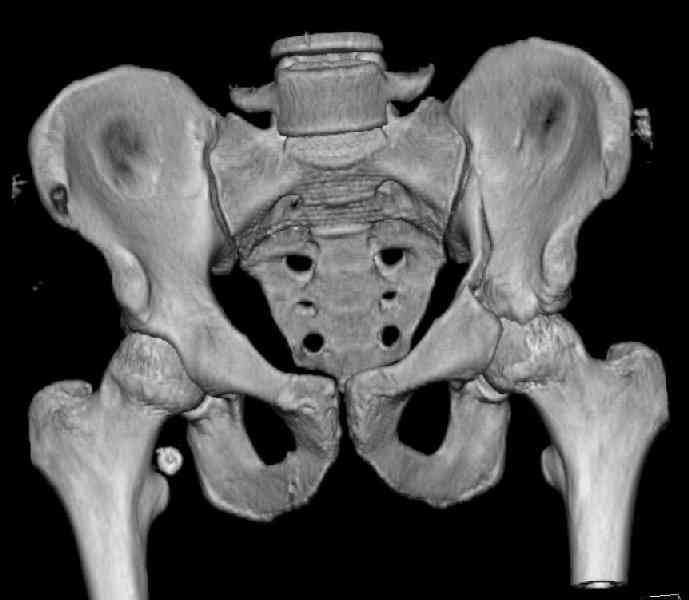

Мужчина 33 лет получил травму в шахте (придавило вагонеткой) 6 недель назад. Изолированное повреждение вертлужной впадины.

В местной больнице отлежал несколько недель на вытяжении. После выписки амбулатрный травматолог направил в институт. На сегодня, похоже, уже имеется неправиильное сращение. См. картинки.

Dear all, A male 23 y.o. injured 6 weeks ago - mine trauma, impacted by a carriage. Isolated injury of the acetabulum. At the initial hosptial was on bed traction some weeks. After discharge visited anotheк orthopaedic surgeon who referred him to our unit. To date looks like a malunion. Images attached. The question is about what to do now - either leave it as is or perform open reduction? If the latter what approach, reduction manoeuvres and fixation would you advice? Thx in advance!